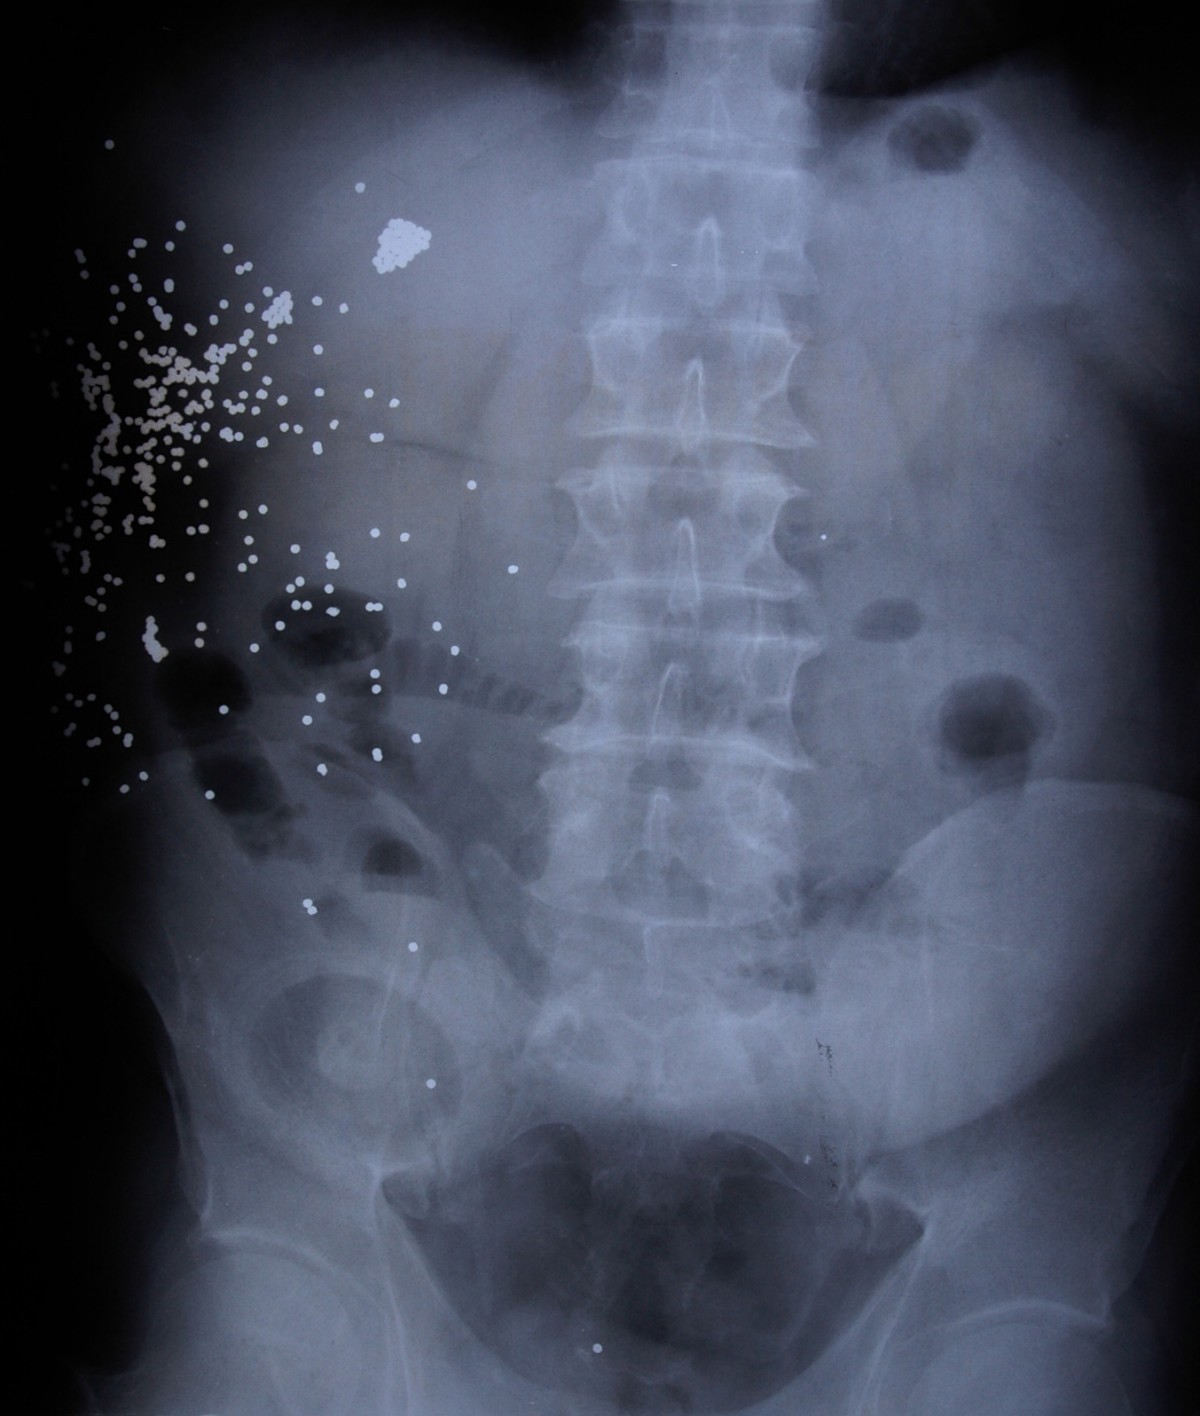

From casesjournal.biomedcentral.com

Abdominal shotgun trauma A case report Cases Journal Full Text Frozen Open Abdomen Relatively recently the concept of “intentional open abdomen” was described and both clinical entities share common pathophysiological and. Scence—is a dangerous postoperative complication. The term “open abdomen” (oa) refers to a surgically created defect in the abdominal wall that exposes abdominal. One of the damage control strategies used to avoid or treat abdominal compartment syndrome is “open abdomen (oa),” where. Frozen Open Abdomen.